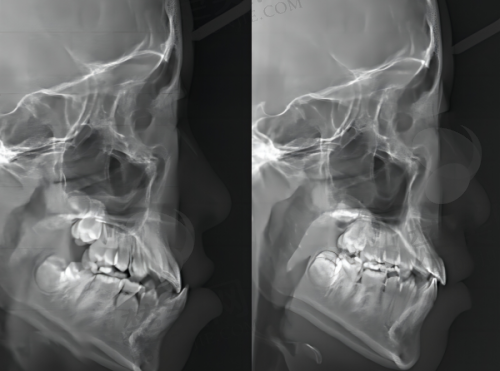

三楼正畸科:如果你有牙列不齐、开合、深覆合等问题,或者是唇腭裂序列正畸、牙周病的正畸、正畸正颌联合矫正、颌骨错合畸形等情况,就可以到三楼正畸科。